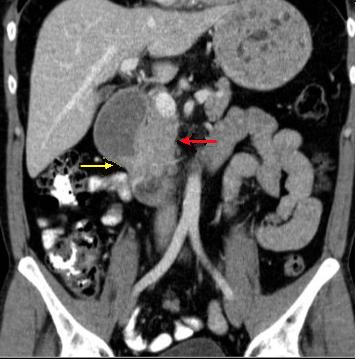

| Tumeur a petite taille

hypo-dense intraluminale de l'intestin ( fleche

rouge ) avec image

d'une masse spicule ( fleche jaune ) mesenterique ( reaction

desmoplastique adjacent ) |

Masse fibrose par

desmoplastique meseterique en forme de

image spiculaire ( fleche rouge ) d'une tumeur

carcinoide de l'intestin . Image TDM en coupe

coronal |

Image d'une masse

fibreuse desmoplastique retractile mesenterique (

fleche jaune ) avec des nodules de calcifies.